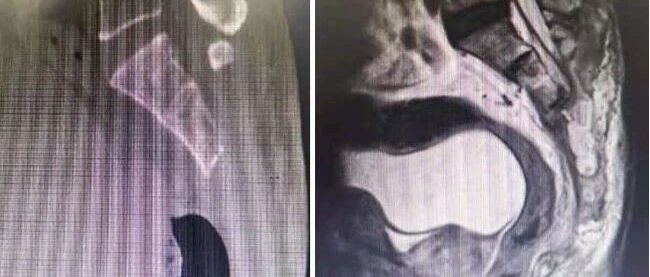

石排医院医生接诊时,发现小玉双侧瞳孔极度缩小,结合特殊气味,迅速判定为有机磷中毒,立即把玉儿的头发剃净,彻底清洗头皮;转至东莞市儿童医院后,医护人员再次为小玉进行了皮肤清洗,并给予相应治疗。